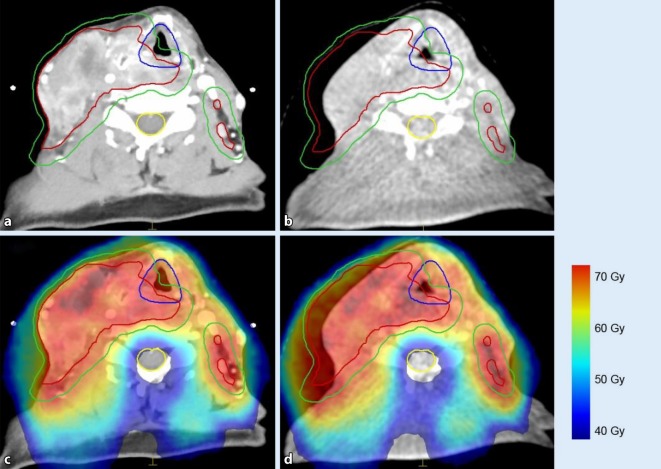

Fig. 2.

Image-guided radiotherapy (RT) for head and neck cancer. Planning computed tomography (a) overlaid with dose (c); same patient in week 5 of treatment (b, d). Although the treated lymph nodes evidently regressed (b), dose coverage is maintained even without adaptation of the treatment fields in this photon-based rotational arc RT (d). Gross tumor volume: red contour; planning target volume: green contour; larynx: blue contour; spinal canal: yellow contour